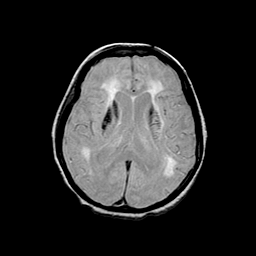

Basal Ganglia Calcification: proton density-weighted MR -- Slice #10

[Home][Help][Clinical] Slice 10